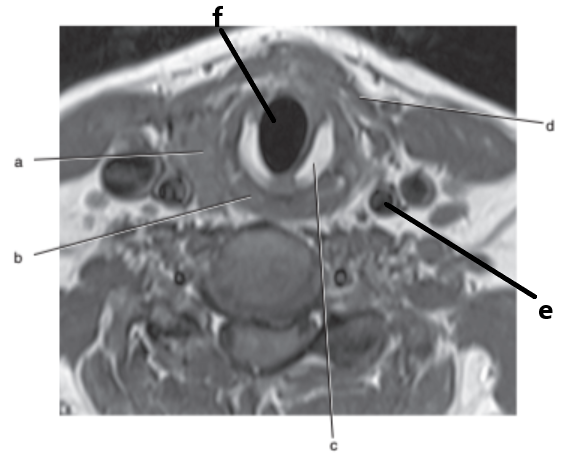

What imaging plane is this ?

transverse

What is letter f ?

Spinal cord

Thyroid gland

What is letter g ?

Vocal cords

What is letter b ?

Esophagus

Trachea

What is letter a ?

Vertebral artery